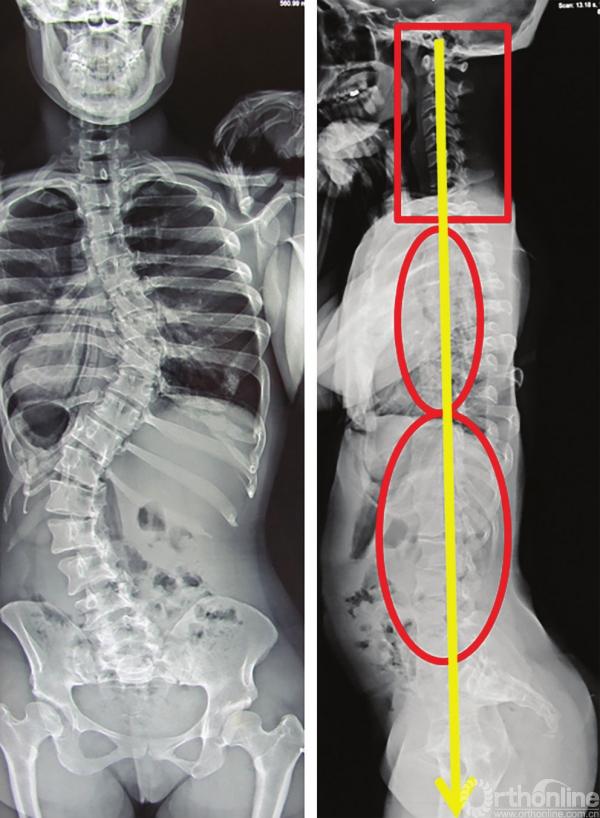

向上力线解释了合并颈椎后凸的特发性脊柱侧弯患者,通常合并有平背表现(图3-36)。

图3-36

图3-36 特发性脊柱侧弯“平背”患者的脊柱力线,颈椎呈后凸状态